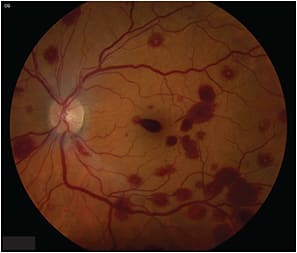

Examination of the right fundus was unremarkable, but the left eye revealed multiple intraretinal white-centered hemorrhages throughout the macula and periphery (Figure 1). We detected no vitritis, retinitis, or vasculitis in either eye.

Figure 1. At presentation, fundus photograph of the left eye with multiple intraretinal white-centered hemorrhages.